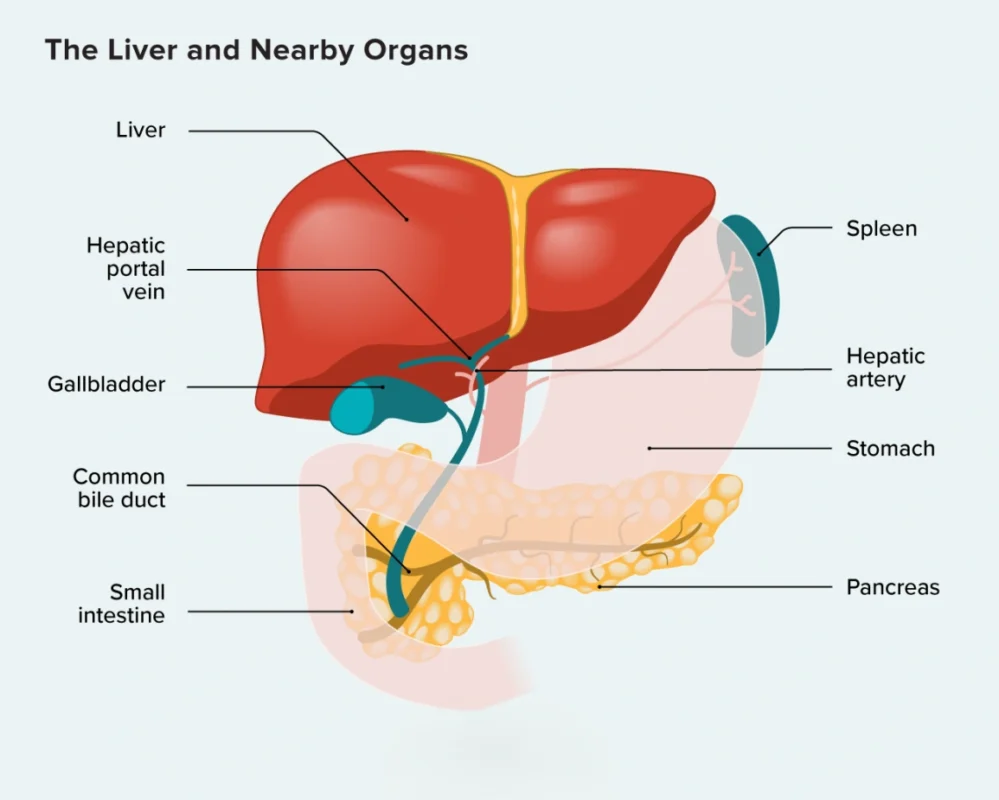

The liver is one of the most important organs in the body, responsible for functions such as detoxification, metabolism, digestion, and blood regulation. Various liver diseases can affect the normal function of this organ and may lead to complications such as portal hypertension, internal bleeding, or fluid buildup.

Our department provides specialized treatments including:

Transjugular Intrahepatic Portosystemic Shunt (TIPSS)

Balloon-Occluded Retrograde Transvenous Obliteration (BRTO)

Splenic Artery Embolization

Variceal Embolization